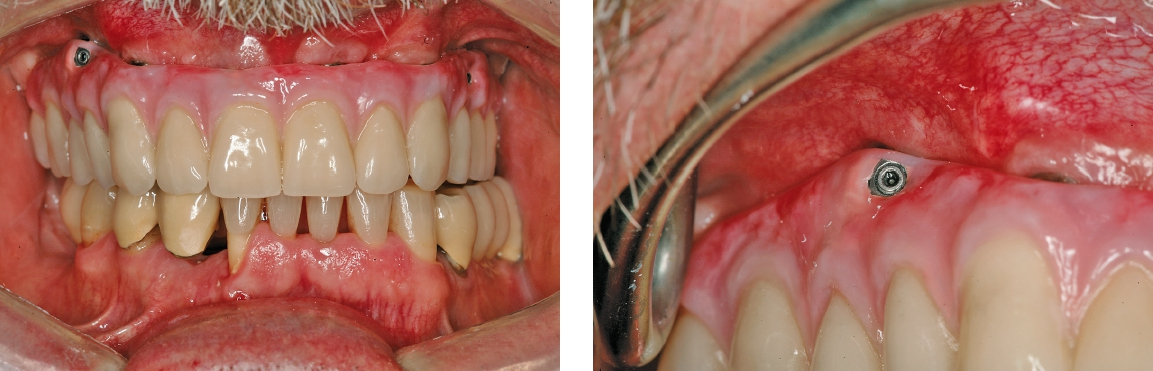

Der Patient konsultierte während der kommenden Wochen regelmäßig die Praxis. Der postoperative Verlauf gestaltete sich problemlos. Nach vier Monaten zeigten sich osseointegrierte Implantate sowie stabile Hart- und Weichgewebeverhältnisse. Für die Herstellung der definitiven Brücke sind unterschiedliche Konzepte möglich. In diesem Fall sollte eine verschraubte Versorgung gefertigt, das Gerüst mit Komposit verblendet sowie die Restauration farblich individualisiert werden. Da schon bei der Herstellung der temporären Brücke festgestellt worden ist, dass die okklusale Verschraubung aufgrund der sichtbaren Schraubenkanäle zu ästhetischen Problemen führt, war eine transversale Verschraubung (Verbolzung) des Zahnersatzes auf den Implantaten angedacht.

Nach einer Überabformung wurde die provisorische Versorgung entnommen und die Situation abgeformt. Für die Evaluation der ästhetischen und funktionellen Parameter des Zahnersatzes war eine Ästhetikeinprobe indiziert. Das Set-up dafür wurde auf einer verschraubten Basis aus lichthärtendem Kunststoff angefertigt. Im Labor erfolgte die Herstellung des Gerüstes unter Berücksichtigung der transversalen Verschraubung. Die Verbindungselemente wurden in das Gerüst eingearbeitet. Grundsätzlich stellt die auf Implantaten verschraubte Restauration eine hohe Anforderung an die Gerüstpassung, da aufgrund der starren Verbindung der Implantate mit dem Knochen ein geringer Krafteinsatz eine hohe Auslenkung zur Folge haben kann. Eine Gerüsteinprobe im Mund bestätigte die spannungsfreie Passung. Es folgte die Verblendung des Gerüstes nach bekanntem Vorgehen. Mehrschichtige Verblendschalen aus einem High-Impact PMMA-Komposit (novo.lign, bredent) und lichthärtende Komposite unterstützten die einfache ästhetische Charakterisierung.

Eingliederung

Das Aufschrauben der definitiven Brücke gestaltete sich problemlos. Nach Abnahme der temporären Versorgung ist die fertiggestellte Brücke über die Prothetikkappen bzw. die Verbolzungen auf den Implantaten befestigt worden (Abb. 5 und 6). Bei den posterioren Implantaten wurde der Schraubenzugang vom Zahntechniker nach vestibulär – außerhalb des sichtbaren Bereichs – gelegt (Abb. 7 und 8). Die anderen Implantate wurden im palatinalen Bereich verschraubt (Abb. 9). Aufgrund der Drei-Punkt-Fixierung ist ein Verkippen oder das Rotieren des Zahnersatzes ausgeschlossen. Da die Schraube in der Sekundärkonstruktion „gefangen“ ist, wird die Anwendung im Mund erleichtert. Ein lästiges Einfädeln entfällt. Bereits mit zwei bis drei Umdrehungen ist eine Schraube fixiert. Weder ästhetisch noch funktionell treten Beeinträchtigungen auf.